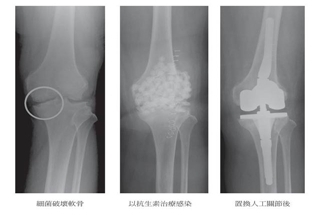

軍官O形腿 關節退化害的!

(優活健康網記者徐平/綜合報導)85歲許老先生為職業軍官退伍,長年飽受膝痛所苦,連腳踏車都無法騎,前幾年不僅無法上下樓梯,走路也開始出現「0形腿」,吃止痛藥不見效,3年前因寸步難行就醫,剛開始打玻尿酸稍有改善,但不到半年膝蓋又開始疼痛,後來接受「機器人手臂膝關節置換術」,術後立即可以下床,隔日就出院,2周後就騎著單車趴趴走,甚至到澳洲爬山。每10個老年人 有7個受膝關節炎之苦老年人膝蓋問題雖不會馬上致命,卻會慢性影響生活品質,並與失智、中風和冠狀心臟病並列為造成老人失能的前4大疾病,據統計,台灣每10個70歲以上老年人,就有7個飽受退化性膝關節炎之苦,帶來疼痛與腿部關節活動的限制,嚴重者甚至無法行走、只能以輪椅代步。台北中山醫院骨科吳濬哲醫師表示,「退化性膝關節炎」是關節軟骨經過多年的使用,造成軟骨磨損、滑囊發炎及增生,高達85%的患者膝關節疼痛,問診後發現超過90%患者會自行吃止痛藥,另外也有超過50%成老人家,誤以為補鈣可以改善退化性膝關節炎。機器人手臂膝關節置換術 降軟組織破壞吳濬哲醫師表示,許多退化性膝關節炎患者擔心「傳統全人工膝關節置換術」的手術傷口大、開刀危險性高,加上顧慮術後會增加子女或家人照顧的負擔而選擇放棄手術,而目前「機器人手臂膝關節置換術」只針對部分磨損、壞損的關節做磨除,保留健康的骨頭、前後十字韌帶及本位感神經組織,大幅降低傷口周圍的肌肉及軟組織拉扯和破壞。